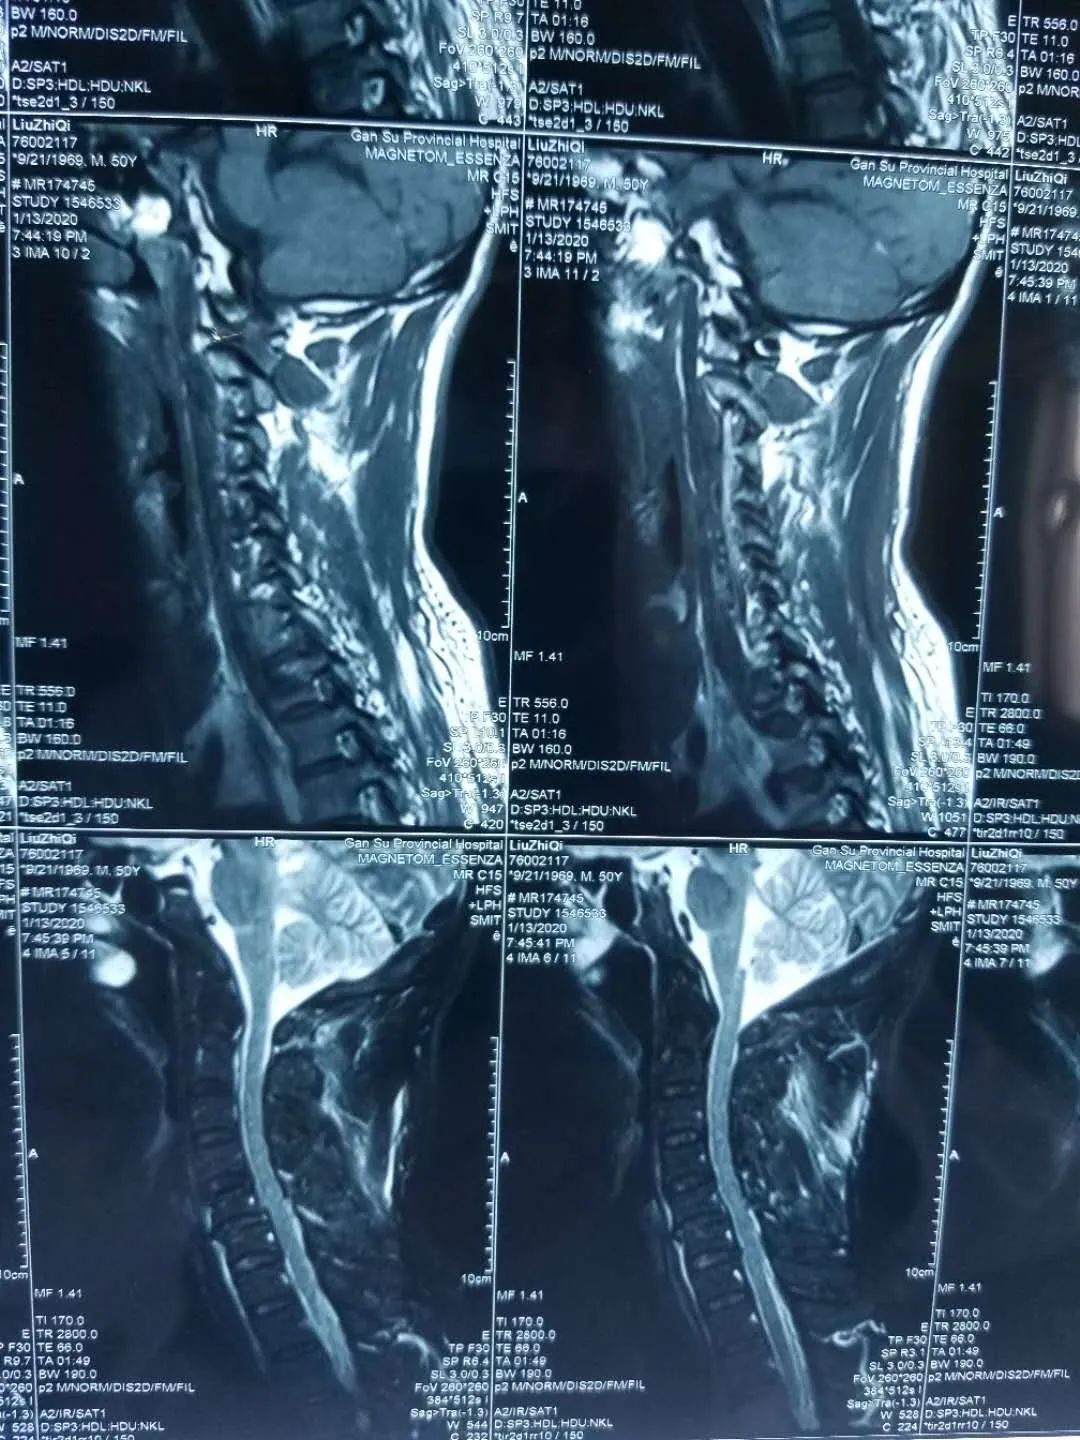

四个多月来,患者根据医生建议一直佩戴颈托休养,但佩戴颈托给患者的生活带来了很大的不便,吃饭困难,睡觉困难,庄稼地里的农活也是被一天天的耽搁。4个月后,患者去当地医院复查,可是带给他们的依旧是不好的消息。复查CT显示:C5椎体前滑脱(Ⅱ°),椎小关节脱位,导致椎管及椎间孔狭窄。椎体滑脱比之前更严重了,而且病人也感觉到手指麻木的症状加重了,并且右胳膊酸困疼痛,当地医院的医生建议患者尽快到大医院治疗,否则会有瘫痪的危险。

患者家属经过多方打听后找到了甘肃省中医院骨肿瘤科李红专主任,李红专给患者详细查体、阅读影像学资料后认为患者颈椎滑脱很容易造成截瘫,伤后4个月滑脱进一步加重,说明颈椎不稳定,患者没有瘫痪已属幸运,如果继续保守治疗,给予头-颈-胸支具固定,一方面防止滑脱再次加重引起患者截瘫,另一方面会给患者生活带来很大不便,严重影响患者生活质量。但如果进行手术治疗,患者已摔伤4个多月,伤处瘢痕粘连严重,滑脱复位困难,单纯前路或后路或前后路联合都可能无法使滑脱复位,且稍有不慎就会损伤到脊髓,导致病人截瘫。

通过仔细查体、阅片、查阅文献资料,李红专团队决定为患者进行手术治疗,5月8日为患者实施颈椎滑脱前-后-前路松解复位前路椎间融合后路钉棒系统固定手术,手术历时6小时,术后患者恢复良好,临床症状消失,四肢感觉、运动功能正常,现患者已经治愈出院,随访患者恢复良好。